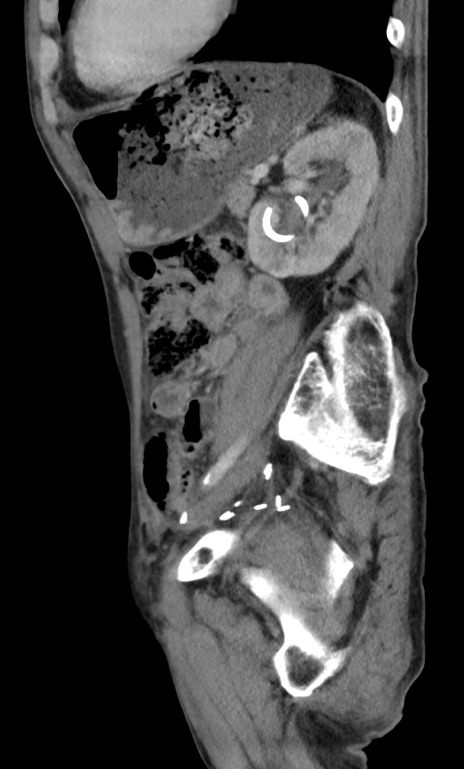

症例3(矢状断像)

【症例】 70歳代男性

【主訴】右鼠径部腫瘤、疼痛

【現病歴】本日朝より上記主訴あり、受診。

【既往歴】膀胱癌にて膀胱全摘、両側尿管皮膚瘻

【データ】WBC 5600、CRP 0.56